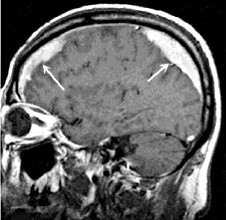

МРТ головного мозга: массивная двусторонняя хроническая субдуральная гематома.

image

Ключевыми методами диагностики субдуральной гематомы являются КТ и МРТ головного мозга. Для острых гематом предпочтительнее КТ, которая выявляет однородную зону повышенной плотности серповидной формы. Со временем гематома разуплотняется, и через 1-6 недель она перестает отличаться по плотности от окружающих тканей. В таких случаях диагноз основывается на смещении латеральных отделов мозга в медиальном направлении и признаках сдавления бокового желудочка.

При проведении МРТ может наблюдаться пониженная контрастность зоны острой гематомы, тогда как хронические субдуральные гематомы обычно имеют гиперинтенсивность в Т2 режиме. В сложных случаях помогает МРТ с контрастированием: интенсивное накопление контраста капсулой гематомы позволяет дифференцировать ее от арахноидальной кисты или субдуральной гигромы.